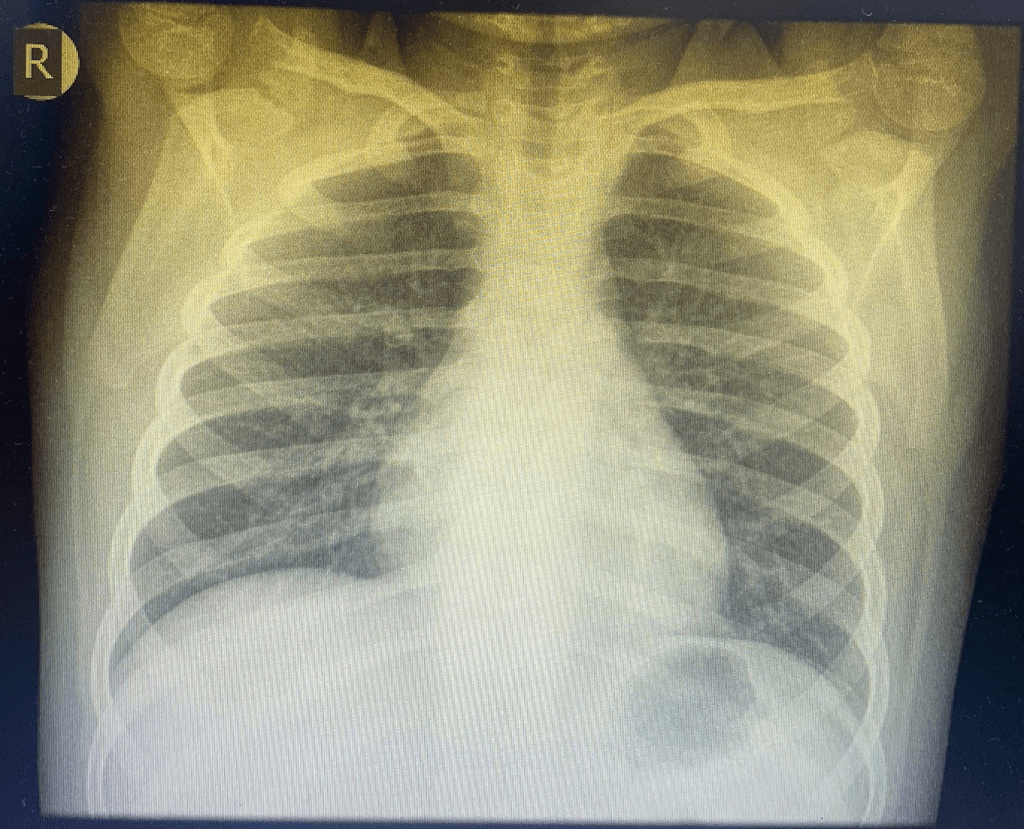

Radiografia toracică

Radiografia pulmonară este considerată standardul de aur pentru confirmarea pneumoniei, în special în cazurile complicate sau când diagnosticul clinic este incert. Aceasta ajută nu doar la confirmarea infecției, ci și la diferențierea tipurilor de pneumonie, ceea ce poate orienta tratamentul.

Cum interpretăm o radiografie toracică?

Radiografia pulmonară normală:

- În imagine, inima este vizibilă în partea centrală (cercul roșu din imagine)

- Zonele negre reprezintă aerul din plămâni, ceea ce indică o funcționare normală a acestora ( săgețile roșii din imagine)

- Oasele (coastele, claviculele și coloana vertebrală) apar mai albe, datorită densității osoase.